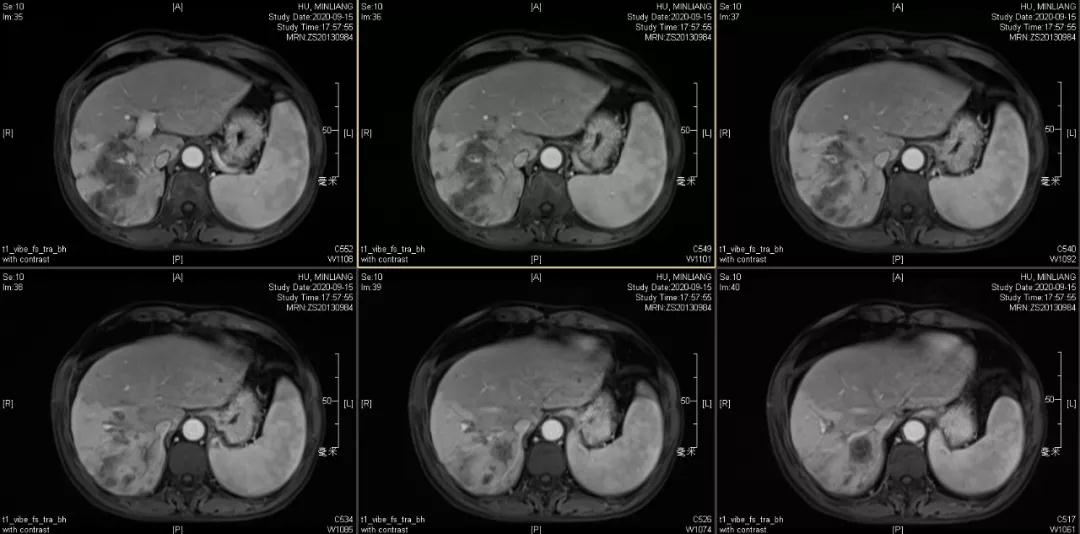

肿瘤学评估(用药后2个月对比6个月):肝内主瘤明显缩小,动脉期强化降低;子灶消失;门脉右支癌栓明显缩小坏死;肺转移灶缩小,大部分消失。

2020-09-15

Δ治疗过程中病灶影像学变化